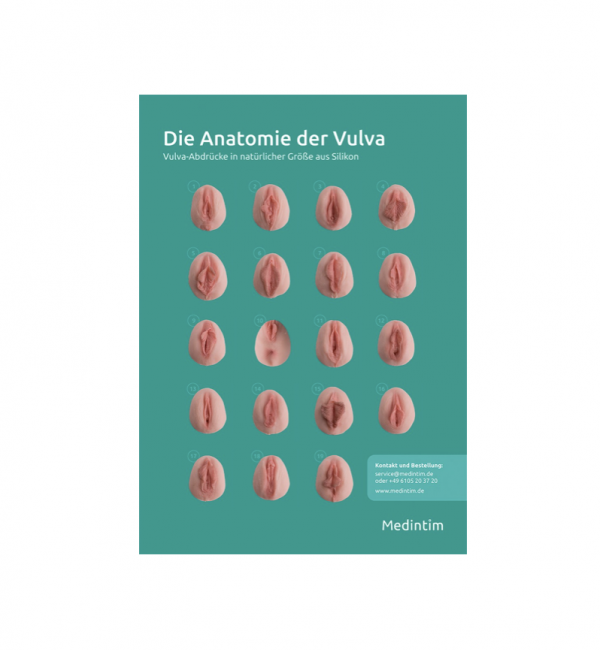

Le 5 misure (integrabili con la sesta, di diametro superiore) favoriscono l’esercitazione progressiva.

I diversi colori facilitano l’identificazione della misura in uso e sono dotati di un comodo astuccio in nylon per riporli.